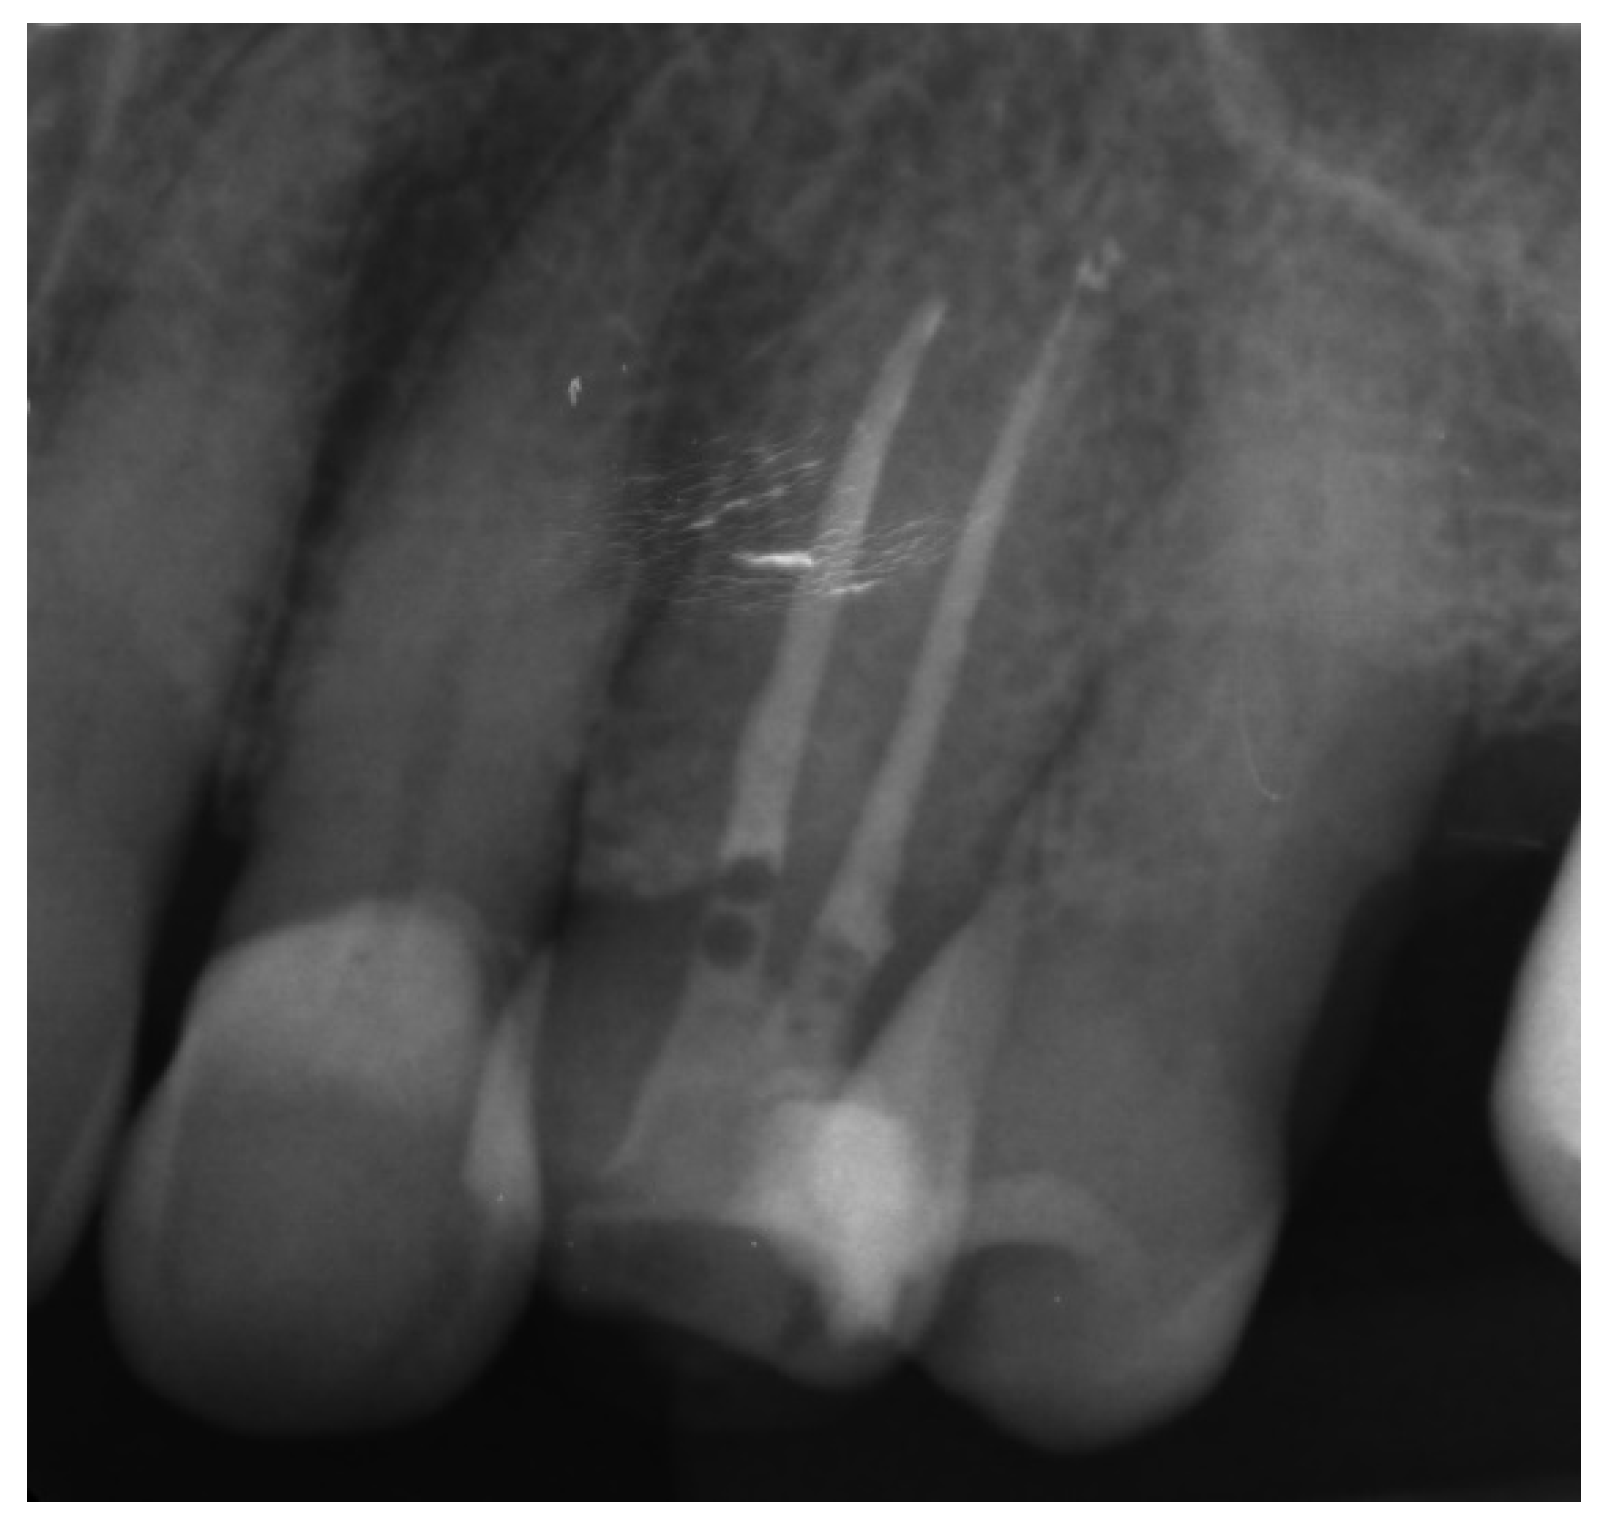

Canal Treatment

Three-Dimensional Treatment Plan and RCT

| Perform a radiographic examination to confirm correct canal access |

| Complete the root canal treatment |